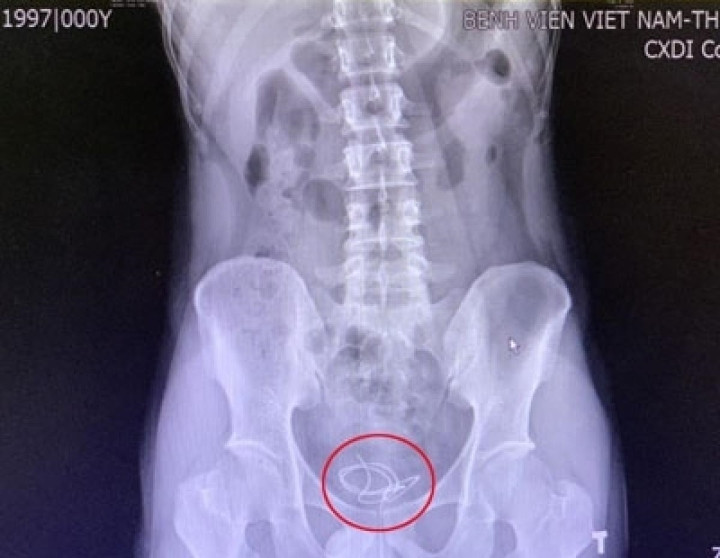

| Hình ảnh siêu âm dây tai nghe bên trong bàng quang bệnh nhân. |